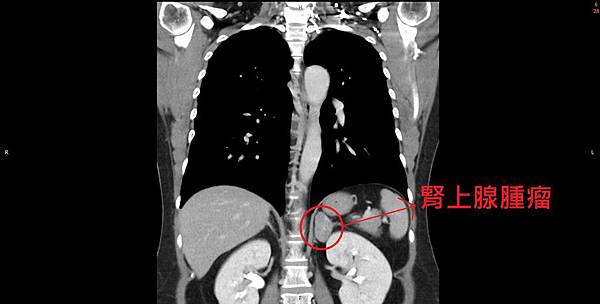

✅ 腎上腺位在人體的深處,幾乎是正中央,一般的超音波能看到的機會少之又少,所以診斷也相當的困難,常常是因為難以控制的高血壓,才會進一步的去查是否有腎上腺腫瘤的可能性,也或者是其他原因安排電腦斷層而意外發現的。

💁🏻♂️ 上面這位病人後來查出是腎上腺腫瘤所引發的「原發性高醛固酮症」,就是經由腹腔鏡腎上腺切除後,隔天的電解質立刻回復到正常了,而且目前也不再需要吃降血壓藥了!